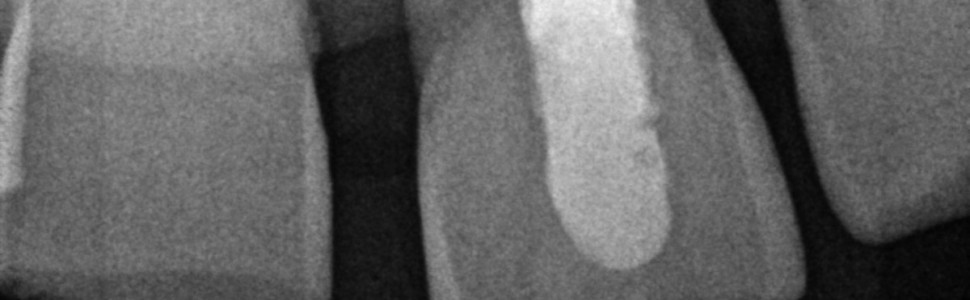

Zwapnienia miazgi zęba są dużym problemem terapeutycznym. Choć często są bezobjawowe, stwarzają dylematy diagnostyczne. Postępowanie zależy w dużej mierze od wystąpienia objawów lub obecności zmian okołowierzchołkowych. Leczenie z użyciem mikroskopu stwarza wyzwanie pod względem preparacji i udrożnienia całej długości roboczej. Prawidłowa ocena przestrzeni endodontycznej i odpowiednia decyzja terapeutyczna mogą rzutować na przetrwanie zęba w jamie ustnej pod względem biologicznym i mechanicznym.

Tooth pulp calcification is a major therapeutic problem. Often asymptomatic, they create diagnostic dilemmas. Management depends largely on the presence of symptoms or periapical lesions. Microscopic treatment poses a challenge in terms of preparation and unblocking the entire working length. Correct assessment of the endodontic space and an appropriate therapeutic decision may affect the survival of the tooth in the oral cavity from the biological and mechanical point of view.